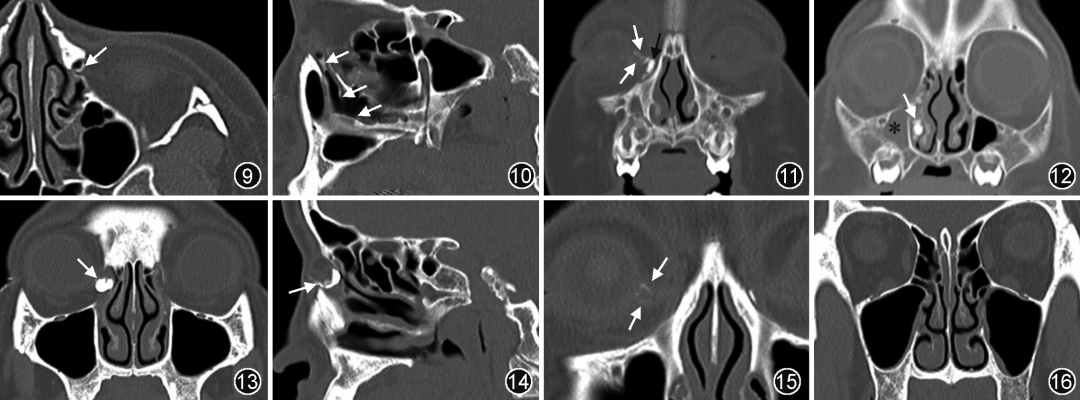

1. 正常泪道的临床及 CT 造影表现(图 9,10):(1)无溢泪病史;(2)泪道周围骨质形态自然;(3)碘对比剂通过泪小管进入泪囊,并能快速、顺畅地流向下鼻道、鼻咽腔或口咽部;(4)泪道内残留少量碘对比剂(证据级别高,强推荐)。

2.鼻泪管阻塞临床及CT造影表现(图11,12):(1)患侧溢泪病史;(2)鼻泪管阻塞位置上游鼻泪管、泪囊和泪小管碘对比剂潴留;(3)下鼻道及鼻咽腔内均无碘对比剂显示(证据级别高,强推荐)。

3. 泪囊阻塞临床及 CT 造影表现(图 13,14):(1)患侧溢泪病史;(2)泪囊阻塞部位上游泪道碘对比剂潴留(证据级别中,强推荐)。

4.泪总管阻塞临床及CT造影表现(图15,16):(1)患侧溢泪病史;(2)结膜囊及上下泪小管显影,碘对比剂在泪囊外侧壁上下泪小管交角处终止(证据级别低,不确定);(3)泪囊、鼻泪管及鼻咽腔未见碘对比剂显示。

图9,10 CT 泪道造影图像。左侧泪道通畅,横断面(图 9)及矢状面(图 10)显示泪囊边缘和下鼻道少量碘对比剂(??)

图11,12 鼻泪管阻塞 CT 泪道造影图像。患儿右眼溢泪病史,冠状面图像显示泪小管(图 11,白??)、泪囊(图 11,黑??)、鼻泪管(图12??)内碘对比剂潴留,下鼻道及鼻腔未见碘对比剂。右侧上颌窦内可见炎症(*)

图13,14 泪囊阻塞CT泪道造影图像。CT 冠状面(图13)和矢状面(图14)显示右侧泪囊内碘对比剂潴留(??),右侧鼻泪管及下鼻道无对比剂显示

图15,16 泪总管阻塞CT 泪道造影图像。右侧泪总管阻塞,冠状面显示上下泪小管无法汇合,上下泪小管见少量碘对比剂(图15,??),泪囊和下鼻道内无对比剂显示(图16)